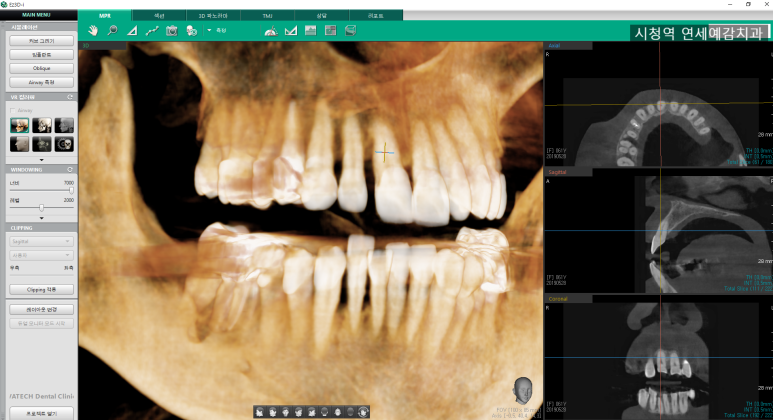

![[시청역/을지로] 임플란트 진단 상담 비용? 관련 이미지 1](https://pub-9f2bb3498faf4d1d8714b41df24753e3.r2.dev/content/clinics/archive/rseeanjxfu/naver_blog/yonseiyegam/assets/by_hash/78ab7767119b7c62c8d65ce1e8ccc71a687e3e889e9e35d2fe68a2bff9a8d983.jpg)

이렇게 파노라마 사진을 통해 임플란트 할 곳에 대해 파악할 수 있습니다.

임프란트에서 가장 중요한 것은 잇몸뼈입니다. 잇몸뼈에 임플란트를 식립해야 하기 때문이죠.

임플란트를 심을 수 있는 어느 정도의 공간이 있고,

신경관을 피해서 심을 수 있는 얼마만큼의 길이가 있는지

윗니라면 상악동 아래쪽의 뼈가 얼마만큼의 길이가 있는지 등을 파노라마를 통해 대략적으로 파악하게 됩니다.

파노라마 엑스레이는 2차원 사진이기 때문에

간단하게 설명하면 좌우간의 관계는 파악이 가능하지만 앞뒤의 길이는 파악이 불가능하여

임플란트수술에는 3차원 ct사진이 필요합니다.

임플란트의 더 자세한 상담을 위해서는 3차원 ct 사진을 대부분 찍게 됩니다.